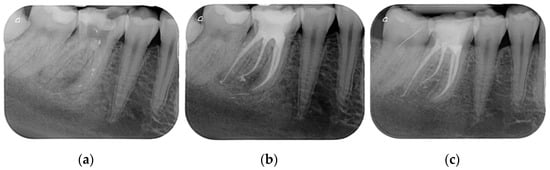

Results showed that 92.61% of ETT did not have any complications up to 18 years (Figure 1, Figure 2 and Figure 3).

Regarding the quality of root filling, 264 teeth (88.59%) showed good filling (Figure 1, Figure 2 and Figure 3) (gutta-percha at the radiologic apex), 22 roots (7.38%) short filling (shorter than 1 mm from the radiographic apex), and 12 (4.03%) long filling (longer than 1 mm of the radiographic apex).

Figure 3. (a) A first lower molar with periapical lesion and in need to be retreated. (b) The molar immediately after being endodontically treated. Four canals (one in a radix entomolaris) were detected and treated. (c) The molar after 4 years. The good health of the periapical areas can be noted. The crown was restored with an adhesive esthetic onlay.

The numbers of failures due to tooth fractures, endodontic, periodontal, or prosthodontic reasons, were limited to 22 of 298 ETT. Of the recorded failures, 14 were reported as repairable; eight were catastrophic failures and, consequently, needed root extraction. The success rate was around 92% (Figure 1, Figure 2 and Figure 3), the survival rate around 4.69%, and only less than 2.69% were irreversible failures. The success and survival rates of this clinical study were a little higher than several others [36,37,38]. Another important aspect related to the failure was the fact that irreversible failures mainly took over in the first two years and within the first 5 years, when cumulated as reversible and irreversible failures. It can be speculated that “biological” complications can come out rather quickly, and periodontal and prosthodontic complications in a longer time, but after 5 years of clinical service, it can be expected that an ETT can stay in clinical service for many more years.